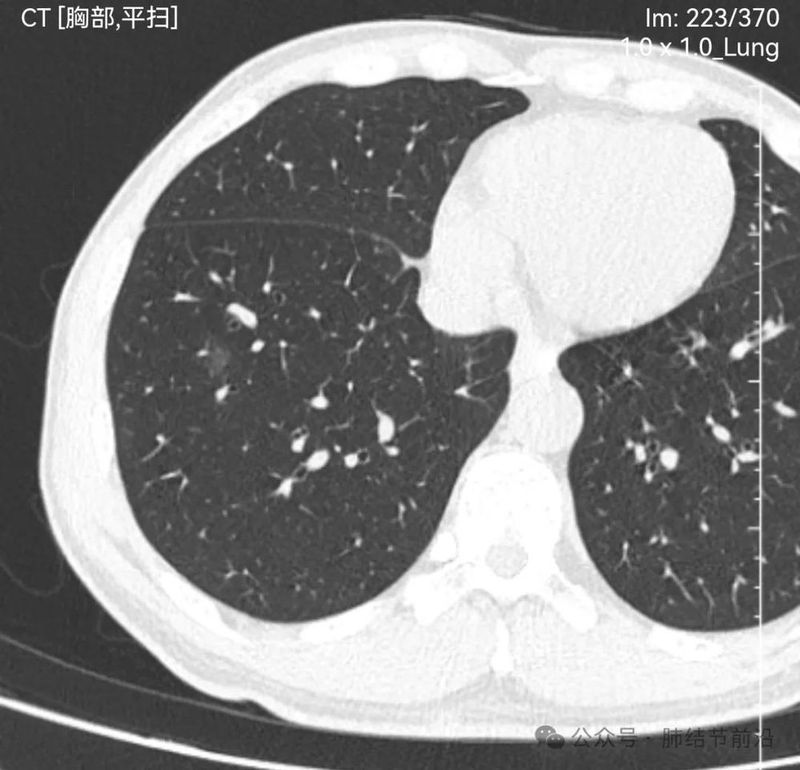

61岁女性,无吸烟史,2024年7月行冠脉CT时发现右肺下叶磨玻璃结节14mm。后续马上复查肺部薄层CT。

见右下肺纯磨玻璃结节14mm。有“血管穿过”、空泡。磨玻璃边界清楚而不毛糙。形态上是典型的肿瘤性磨玻璃,以微浸润腺癌可能大。